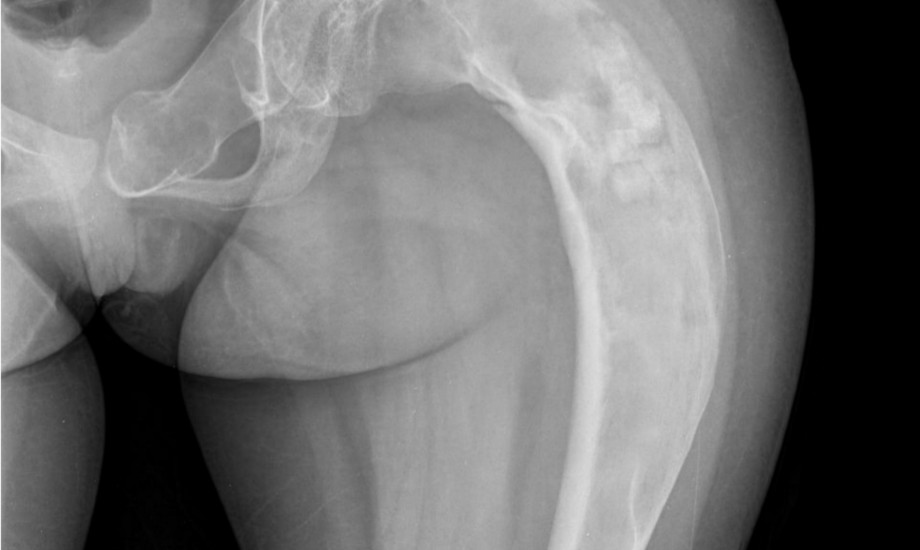

Ein 9-jähriger Junge mit wiederholten Frakturen, ein 8-jähriges Mädchen mit vaginaler Blutung im Kindesalter und eine 7-Jährige mit zunächst einseitiger Brustentwicklung – drei Kinder, drei scheinbar unterschiedliche Leitsymptome. Doch hinter allen Fällen steckt die gleiche seltene Ursache.